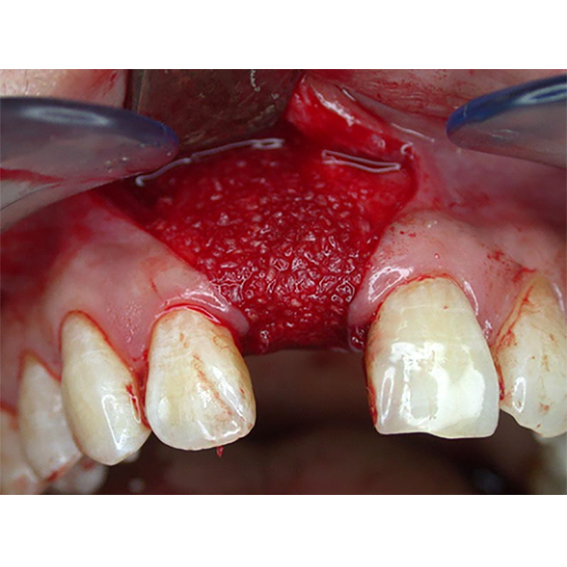

Pure titanium membrane of ultra-thin thickness of about 10 microns (0.01mm). Totally inert, biocompatible and non-biological thus removing the fear of disease transmission from collagen of bovine source. It allows ease of handling and adaptation over the operative site. Because of its mouldability, it does not require pin or screw fixation, thus avoiding the risks of pin or screw swallowing or aspiration. Excellent clinical performance in guided tissue regeneration. Resistance to infection after exposure. Primary wound closure is not necessary. No tissue reaction or wound infection.